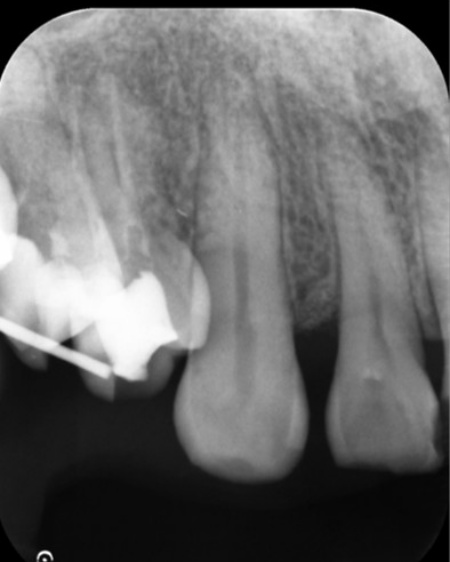

レントゲンを撮影したところ、歯の周囲の骨が溶けて歯ぐきの深い部分にまで歯石が付着していることが確認できました。

半年後のレントゲン検査では、失われていた骨の部分に新しい骨の形成が認められ、歯ぐきの腫れや出血も改善していました。